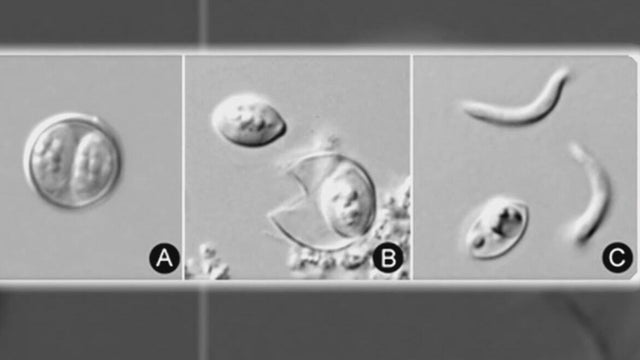

An investigation into cyclospora cases has expanded into seven Michigan counties, as health officials seek to determine the cause of the gastrointestinal illness.

Officials say the source of the infection is currently unknown. The department did not say how many cases were confirmed in the county.

Over 170 recent cases of an intestinal illness linked to cyclospora are under investigation in Michigan. Here's what we know so far.